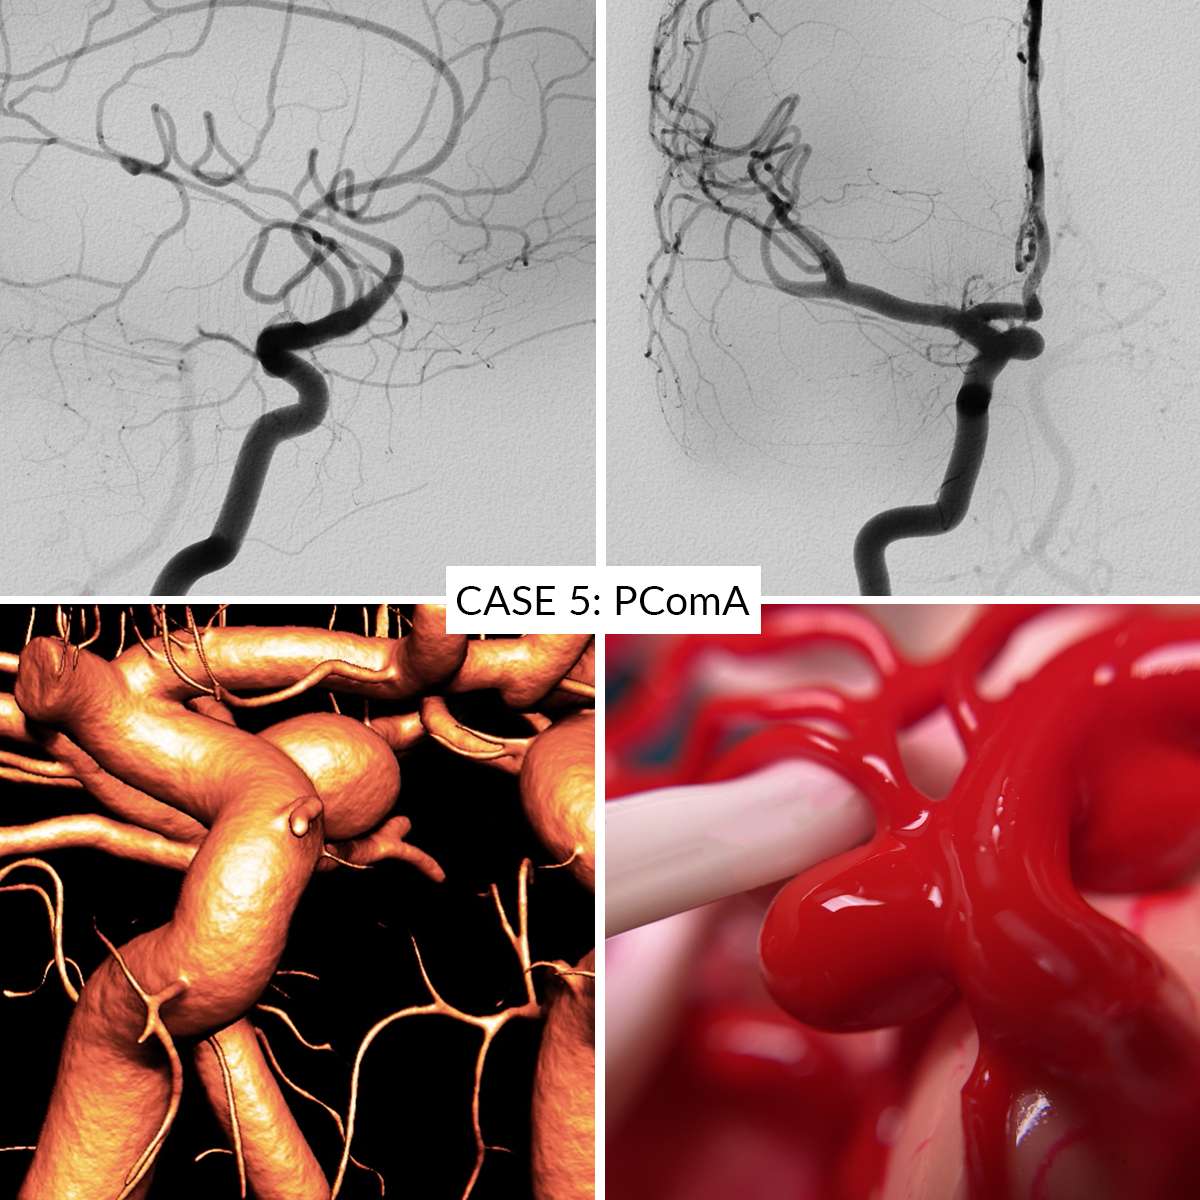

Case 5 : Posterior Communicating Artery

In the AneurysmBox simulator you can operate 5 different aneurysm cases:

- Case 5: Posterior Communicating Artery

Aneurysms are clippable unlimited number of times. Remove the clips gently to avoid damaging the aneurysms.